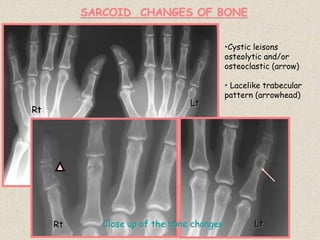

SARCOID CHANGES OF BONE

Rt

Lt

Rt Lt

Close up of the bone changes

•Cystic leisons

osteolytic and/or

osteoclastic (arrow)

• Lacelike trabecular

pattern (arrowhead)